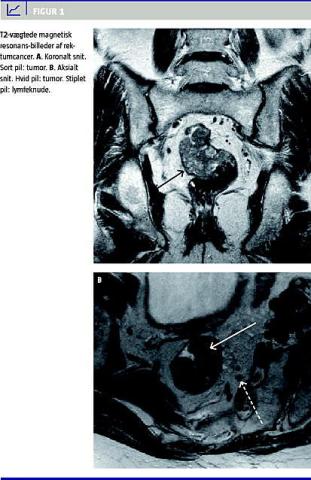

Sagittale, koronale og aksiale T2-vægtede fast spin-echo -sekvenser er herefter foretaget med 32 cm stort billedfelt (field-of-view), 3-4 mm snit med 1 mm interslice-gap , TR/TE på 4.000-4.700/99-132, en 352 × 512 matrix, to akkvisitioner, ingen fedtsuppression (Figur 1 ). Ikke alle patienter har fået udført samtlige sekvenser.